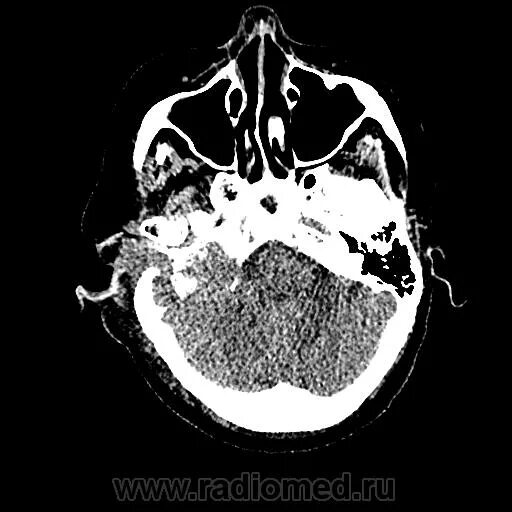

Мрт височных костей в режиме dwi